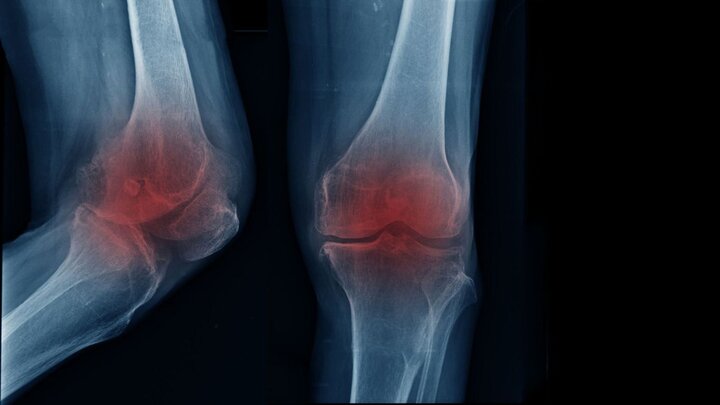

متخصص ارتوپدی و فلوشیپ جراحی زانو با بیان اینکه مفصل زانو یکی از فعالترین بخشهای بدن به شمار میرود و در طول زندگی فشار زیادی را تحمل میکند، تصریح کرد: با گذشت زمان و افزایش سن، لایه غضروفی این مفصل به تدریج نازک و فرسوده میشود و همین روند میتواند زمینهساز بروز آرتروز یا ساییدگی زانو باشد.

اکبری اقدم با بیان اینکه زمانی که این غضروف کارکرد طبیعی خود را از دست بدهد، حرکت مفصل با مشکل همراه و درد و محدودیت حرکتی ظاهر میشود، ادامه داد: بروز آرتروز زانو همیشه به یک عامل مشخص محدود نمیشود و دلایل گوناگونی در ایجاد آن نقش دارند.

متخصص ارتوپدی و فلوشیپ جراحی زانو با تاکید بر اینکه شایعترین علامت آرتروز زانو درد است که به طور معمول در مراحل ابتدایی هنگام راه رفتن یا فعالیت بروز میکند، اضافه کرد: با پیشرفت تخریب غضروف، شدت درد افزایش مییابد و ممکن است حتی در حالت نشسته یا استراحت نیز فرد را آزار دهد.

اکبری اقدم با بیان اینکه علاوه بر درد، احساس خشکی مفصل به ویژه پس از بیدار شدن از خواب، کاهش دامنه حرکتی و دشواری در انجام حرکات روزمره نیز از نشانههای رایج این بیماری محسوب میشود، افزود: اگرچه افزایش سن نقش مهمی در ابتلاء به آرتروز زانو دارد، اما سبک زندگی نیز تأثیر قابل توجهی در زمان بروز آن ایفا میکند.